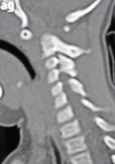

- Figura 4. Tomografía reconstrucción 2D. Muesta inestabilidad C1-C2. Hipoplasia de Odontoides